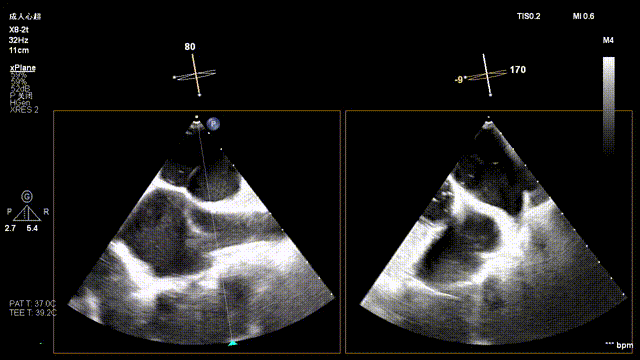

Preoperative precise assessment by transthoracic and transesophageal echocardiography (TTE/TEE) revealed:

Mitral valve: severe functional regurgitation (4+), effective regurgitant orifice area (EROA) 0.52 cm², regurgitant volume 68 mL.

Tricuspid valve: Type IIIb quadricuspid malformation with insufficiency, secondary severe regurgitation (4+), mild annular dilatation (mean diameter 40 mm), mean vena contracta 10 mm. Regurgitant orifices are located at anteroseptal, central, and posteroseptal regions, with marked enlargement of the right atrium and right ventricle.

Mitral Valve Repair Stage: Via the transfemoral venous approach, a 4.0 cm atrial septal puncture was performed, and one mitral valve clip was selected. The unique feature of wide-angle deployment effectively resolved the issue of excessive leaflet tension during valve clip closure. Under the precise guidance of ultrasound, one clip was successfully implanted at the site of the widest regurgitation in the A2-P2 segment of the mitral valve. Immediate postoperative TEE assessment showed that mitral regurgitation was reduced to trivial (1+), the mean transvalvular pressure gradient was only 3 mmHg, and pulmonary venous retrograde flow was significantly improved.

Preoperative Imaging

Mitral regurgitation

3D color Doppler

Mitral valve Zone 2

Color Doppler of Mitral valve Zone 2